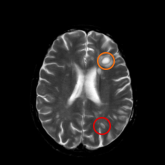

An MRI scan is an important tool used to help confirm an MS diagnosis. There are 2 types of MRI scans used to see lesions:

T2-weighted MRI scans shows all lesions in the central nervous system. An orange circle points out Black hole while a red circle points out T2-w lesions.

T2-weighted scans shows all lesions in the central nervous system: ones that are old and inactive as well as ones that are new.

Black holes T2-w lesions